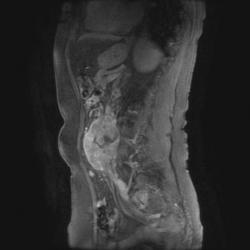

Женщина 47 лет, в течении долгого времени страдала от головных болей. В последние несколько месяцев - прогрессирующая потеря зрения (на оба глаза).

T2 ВИ Sagittal

Presented images are corresponded for cerebral (right temporal-occipital region) neoplasia; high grade glioma is most suggested.

Глиальная опухоль.